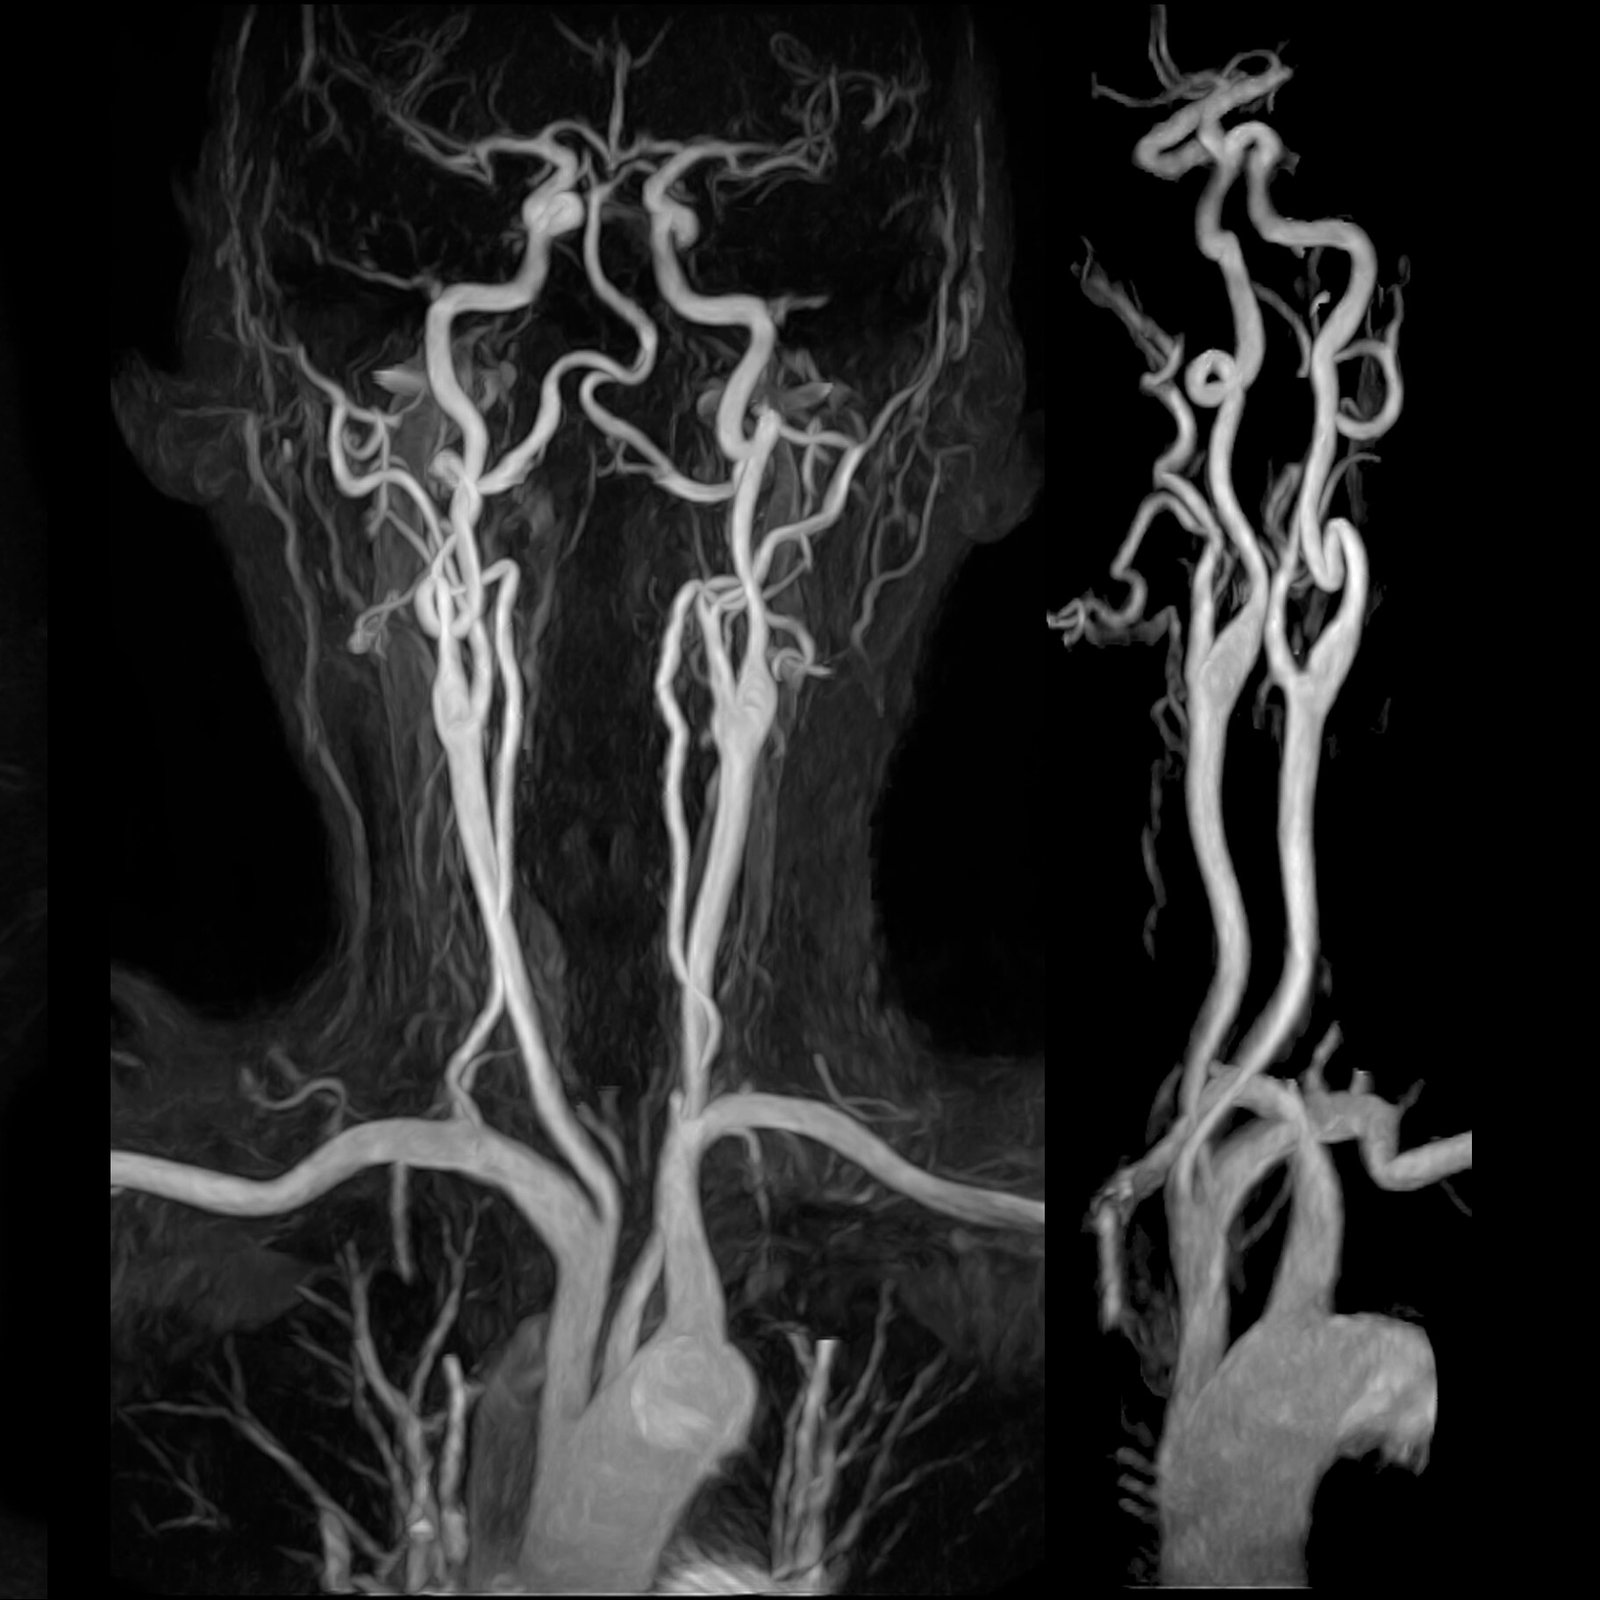

Neurovascular